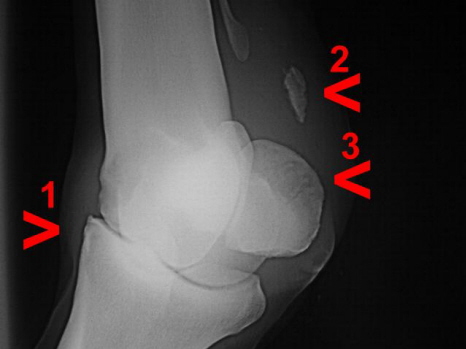

Verkalkung im Fesselträger, Arthrose Fesselgelenk